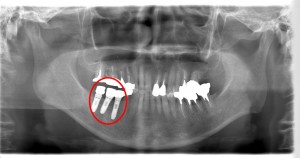

下顎臼歯部のインプラント治療と上顎臼歯部の審美治療

60代 女性 A様

右下の奥歯の欠損と右上の奥歯の銀歯を白くしてほしいということで来院されました。

■術前レントゲン写真

右下に3本インプラントを埋入し、3か月後に右下と右上にセラミックの歯をセットしました。

■術後レントゲン写真